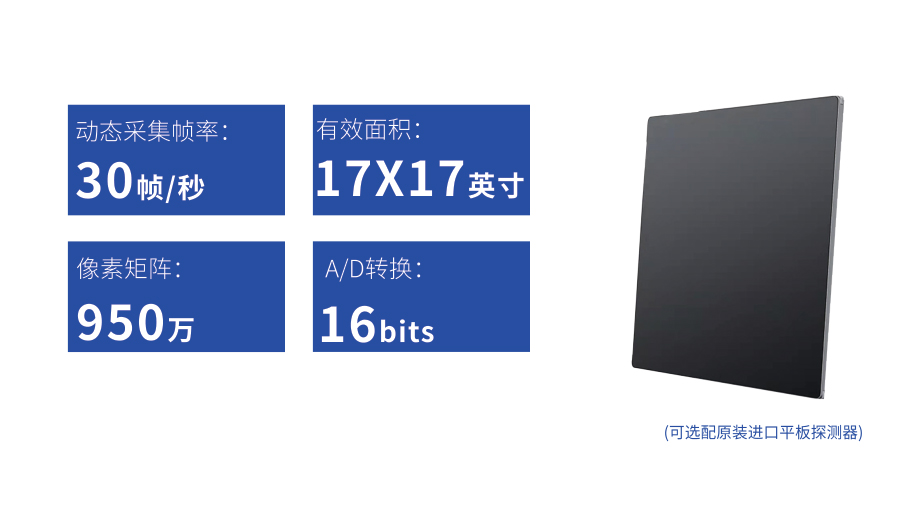

● 17*17英寸的超高清像素動態平板探測器,更大的視野范圍,無需移動即可觀察整個動態過程,避免拖尾、噪聲對圖像的影響;

● 高效動態平板技術,圖像不會有幾何畸變,提供高分辨率和精確的圖像,為醫生臨床診斷提供精準依據;

● 最高幀速可達30幀/秒,動態采集清晰流暢,避免漏診、誤診情況的發生;

● 在可視過程或回放過程中,如發現疑似病灶,可進行毫秒級高清點片,隨時抓取單幀圖像,精準捕抓病灶。